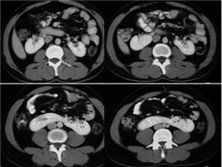

2.CT檢查可清楚顯示腎盂方向異常並根據腎盂朝向可明確此腎臟異常旋轉是前位前中位後位還是側位